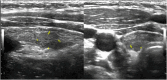

Fig. 1

Parathyroid or thyroid ultrasonography demonstrates a 0.9 × 0.4 × 0.6 cm isoechoic nodule inseparable from posterior or mid right thyroid lobe. No significant internal color flow.